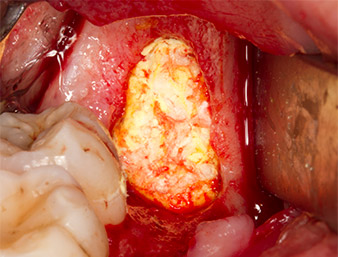

To obtain autogenous material for subsequent wound treatment, healthy bone chips were harvested from the surroundings of the root remnant with a piezo surgical instrument (Piezomed B5) (Fig. 5).

The autogenous tissue was removed with the scraper-shaped section of the working part of the instrument and stored in a physiological saline solution until further use (cf. Fig. 13).

Subsequently, the autogenous bone tissue (Fig. 13) was placed into the alveole and the surrounding bone defect (Fig. 14). Collagen fleece covered the bone chips up to bone level as protection for the exposed nerve (Fig. 15). Sutures using vicryl thread, USP 4.0, were used to close the opened up soft tissue (Fig. 16). An Ibuprofen preparation (Seractil 400 mg, 3x1) and an antibiotic consisting of amoxicillin and clavulanic acid (Augmentin 1 g, 2x1) were prescribed postoperatively.